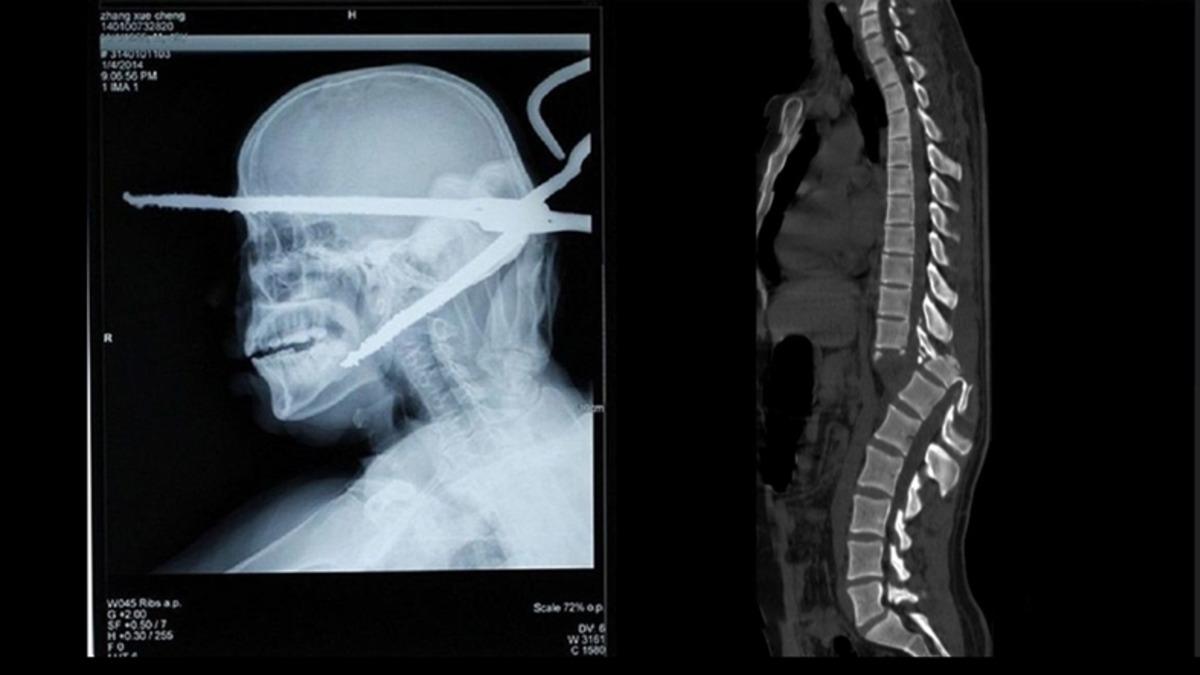

- Ters giden bir soygun sonucunda kafasına bıçak saplanan bir adam.

- Bir adamın arkasından atılan ateş maşası, arkadan girip önden çıkmış.